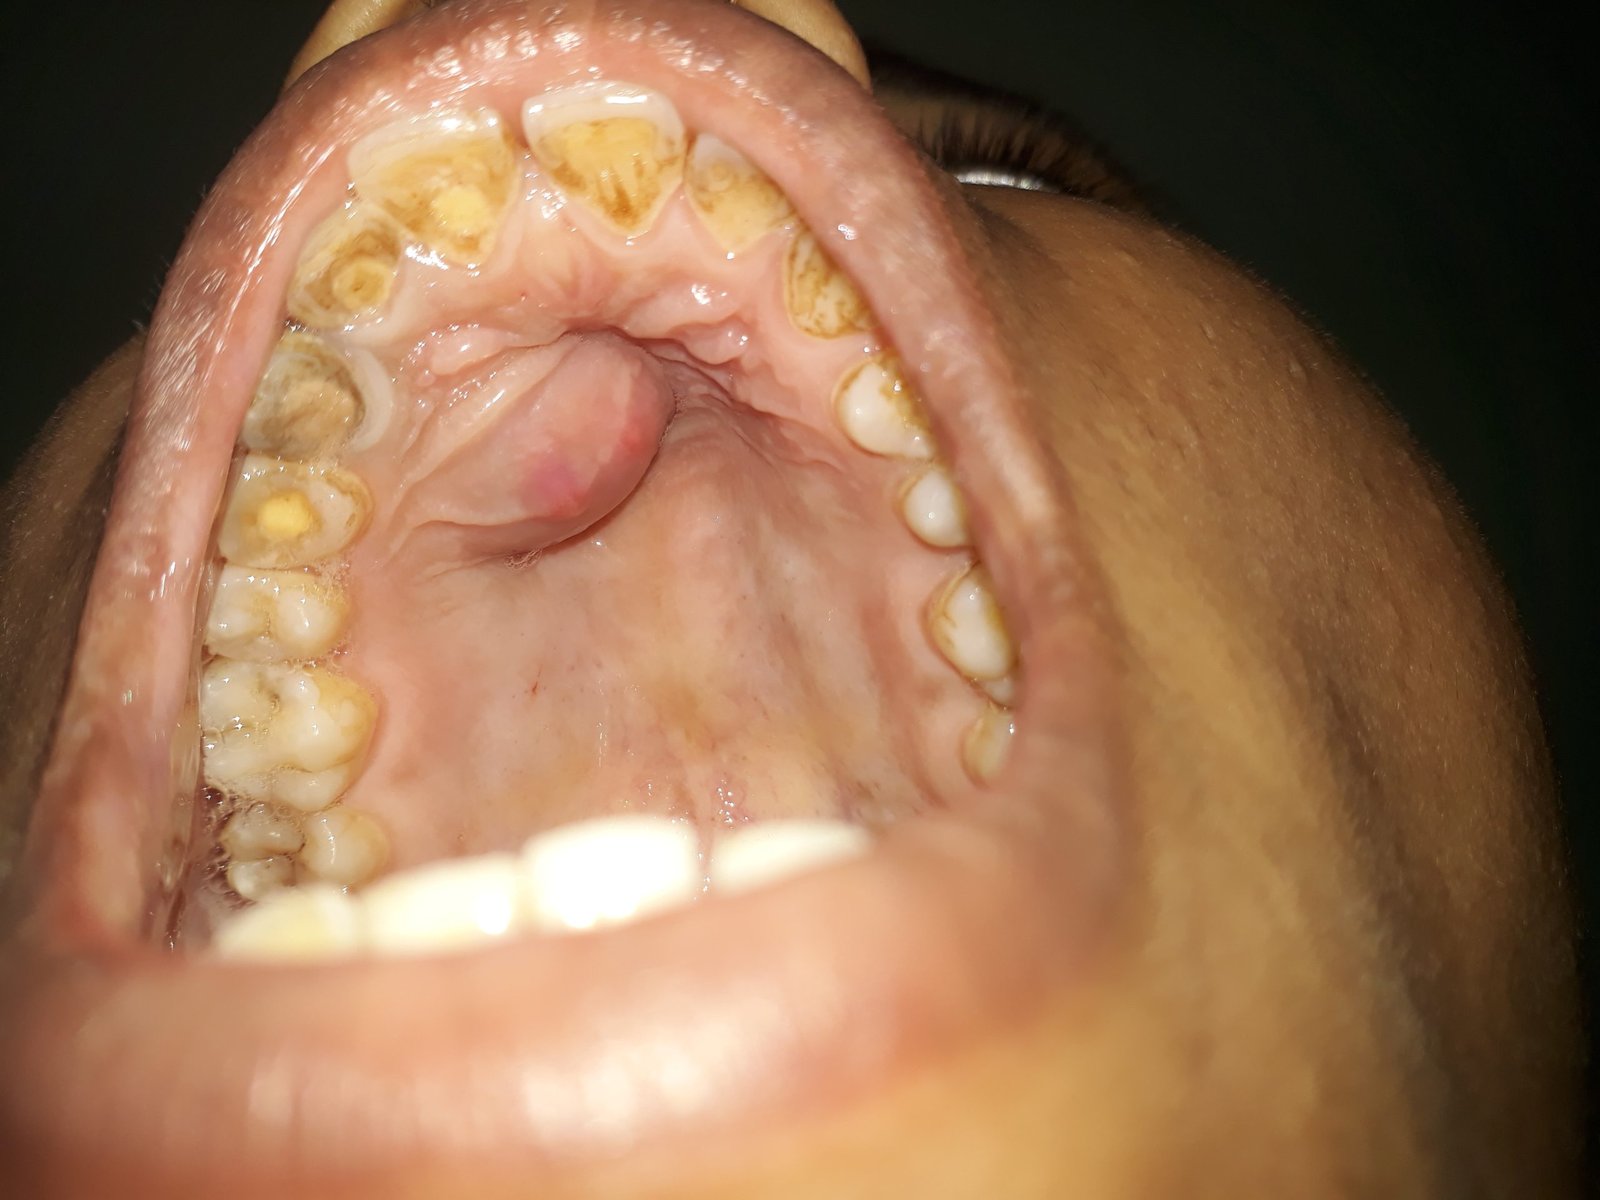

Ranula

A ranula is a fluid collection or cyst that forms in the mouth under the tongue. It is filled with saliva (spit) that has leaked out of a damaged salivary gland. Salivary glands are small structures around the mouth which make saliva.

Saliva should drain from these glands directly into the mouth. If one of these glands is damaged then the saliva leaks out into the tissues next to the gland forming a cyst or bubble near the gland. This cyst is called a ranula.

Small, simple ranulas that don’t cause problems may not require treatment. Some cysts may disappear on their own. Treatment is necessary, however, for enlarged simple ranulas, especially when swelling interferes with swallowing or speaking, and for most plunging ranulas.

Treatment includes Needle aspiration, Incision and draining, Marsupialization and Surgical removal of ranula depending on severity and size of the ranula.